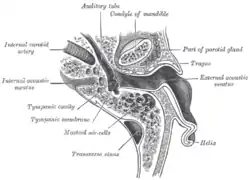

Orientation and relations

The tympanic membrane is oriented obliquely in the anteroposterior, mediolateral, and superoinferior planes. Consequently, its superoposterior end lies lateral to its anteroinferior end.

Anatomically, it relates superiorly to the middle cranial fossa, posteriorly to the ossicles and facial nerve, inferiorly to the parotid gland, and anteriorly to the temporomandibular joint.

External and middle ear, right side, opened from the front (coronal section)

External and middle ear, right side, opened from the front (coronal section) Horizontal section through left ear; upper half of section